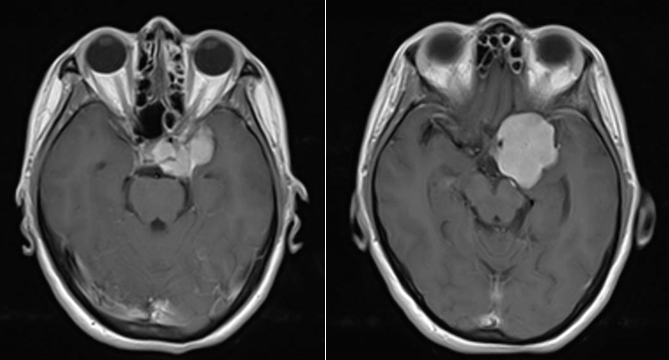

现病史:患者20天前无明显原因出现鼻酸,伴有异味感,继之出现全身不适,呈发作性,每次持续约1分钟左右,发作时意识清、精神可,对发病时情况记忆模糊,共发作3-4次,无意识模糊、复视。颅脑MRI平扫+强化示:鞍上池左侧可见不规则等T1等T2信号影,DWI呈等信号;明显均匀强化,与前床突、颈内动脉关系密切。

诊断:左侧蝶骨嵴脑膜瘤;继发性癫痫。

Al-Mefty教授根据肿瘤的起源和肿瘤与颈内动脉之间是否存在蛛网膜界面,将前床突-蝶骨嵴内侧的脑膜瘤分为三型,这是目前最为经典和广泛认可的分型。ICA在前床突内、下侧方从海绵窦穿出,经过内环与外环(或上环与下环)而后进入硬膜下腔,内外环之间约1-2mm,该节段缺少蛛网膜覆盖。起源于这一小段的脑膜瘤被分为1型前床突脑膜瘤。1型典型的生长方式是包裹ICA,并向颈内动脉分叉部方向生长,包裹近端大脑中动脉。由于肿瘤与颈内动脉之间缺乏蛛网膜,所以它紧密黏附在ICA的外膜上,以至于分离困难,导致手术治愈率相对较低。该患者主体属于1型前床突脑膜瘤,但是因其部分侵入视神经管内,兼有3型的特点,严格讲其属于1-3复合型脑膜瘤。该患者经左侧翼点入路肿瘤切除术,实现肿瘤近全切除,术后未再出现癫痫发作,脑电图无异常,后逐渐减用停用抗癫痫药物,现已持续随访4年余,未见肿瘤复发。